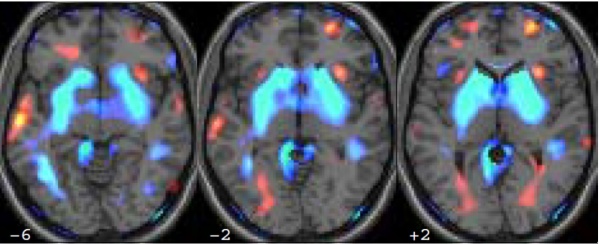

DTI Tractography of Striatal Connectivity in XDP: Relationship to Striatal Compartments and Disease Characteristics

Anne J. Blood, PhD Massachusetts General Hospital

Norbert Brueggemann, MD University of Luebeck, Germany